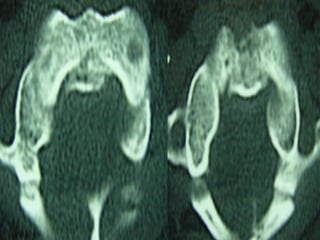

CT SCAN

• TThhee mmoosstt aaccccuurraattee

• EEssppeecciiaallllyy ffoorr ttrraannssvveerrssee ffrraaccttuurreess

• UUsseeffuull ffoorr ddeetteeccttiinngg llaarrggee ddeeffeeccttss aass ttaarrlloovv ccyyssttss

• DDiiaaggnnoossiiss ooff ccooeexxiissttiinngg mmaalliiggnnaanntt lleessiioonnss